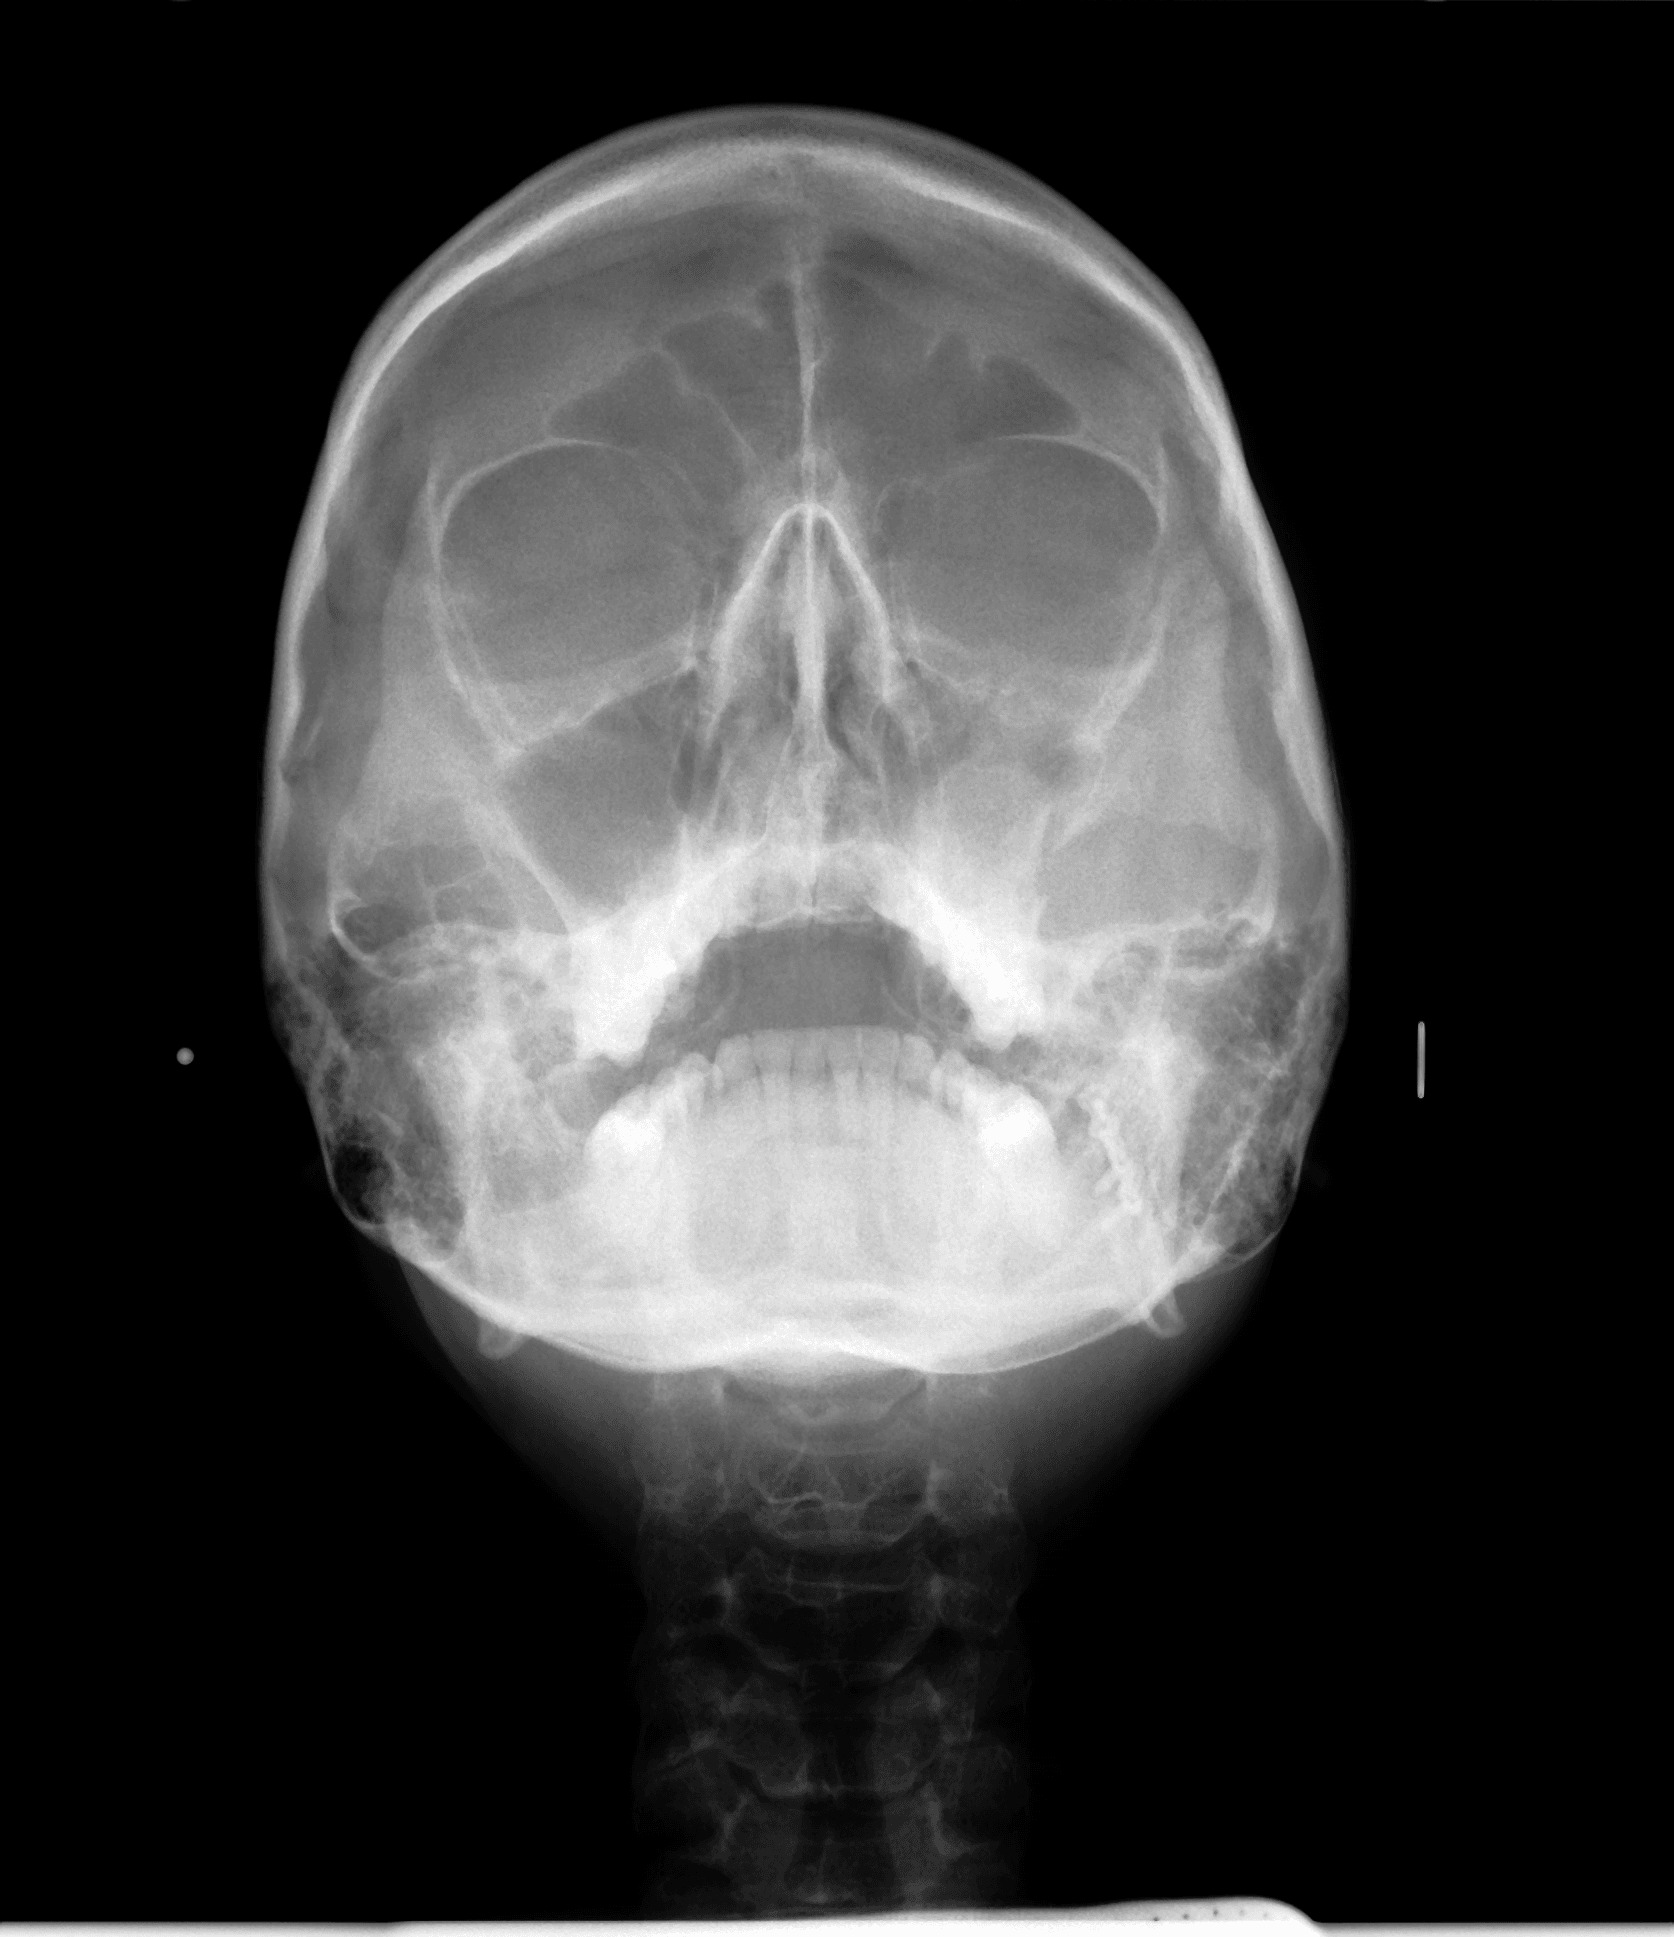

Снимка на синуси

Снимката на синусите обхваща максиларните и фронтални синуси. По нея се прави оценка за състоянието както на самите синуси, така и за проблеми в тях, причинени от заболявания на зъбите.